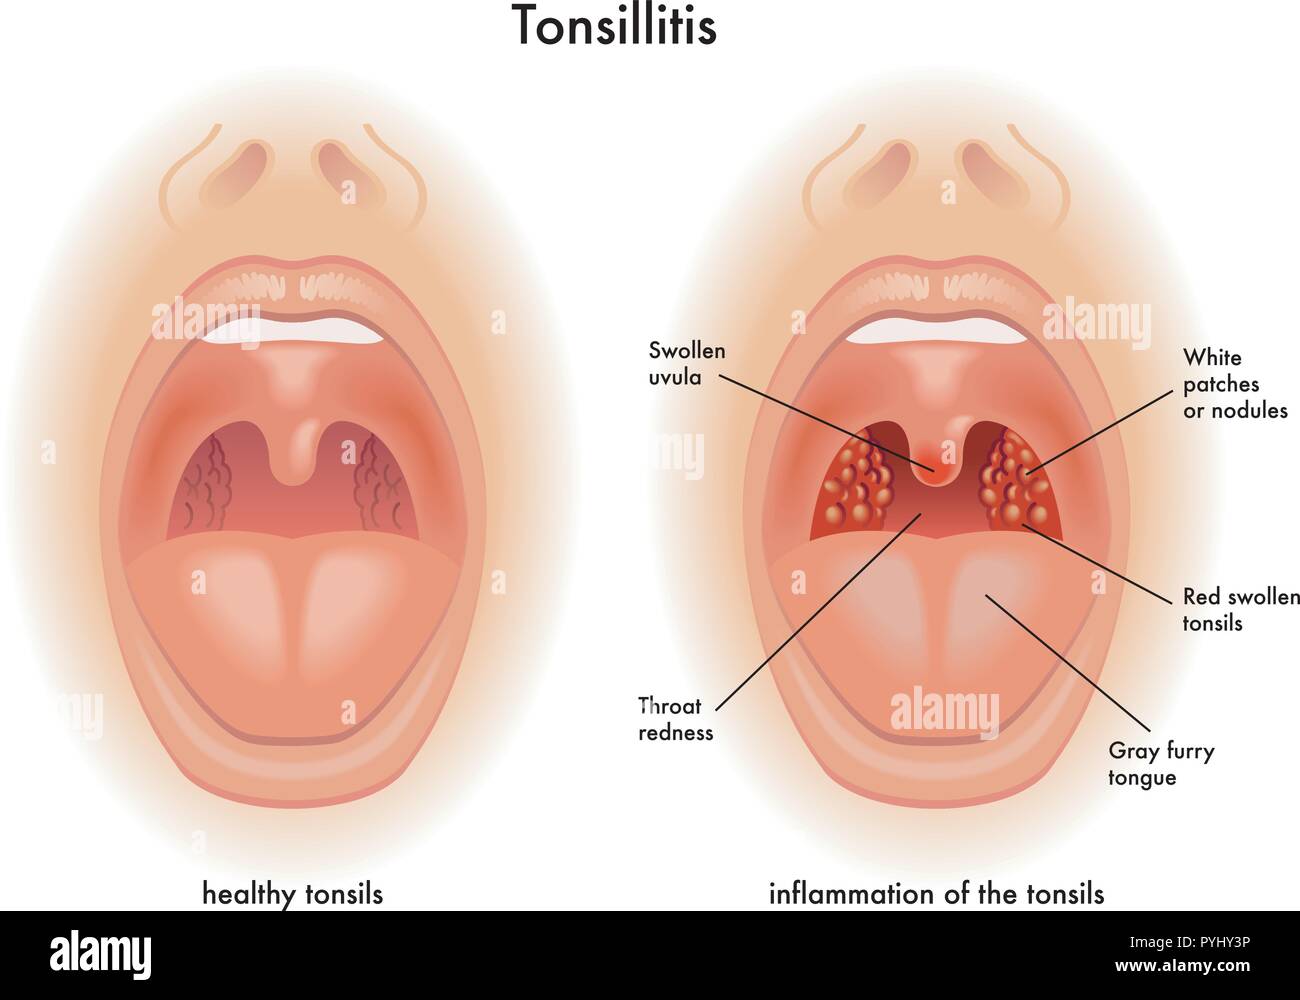

Medizinische Darstellung der Symptome der Mandelentzündung Stock Vektorhttps://www.alamy.de/image-license-details/?v=1https://www.alamy.de/medizinische-darstellung-der-symptome-der-mandelentzundung-image223514586.html

Medizinische Darstellung der Symptome der Mandelentzündung Stock Vektorhttps://www.alamy.de/image-license-details/?v=1https://www.alamy.de/medizinische-darstellung-der-symptome-der-mandelentzundung-image223514586.htmlRFPYHY3P–Medizinische Darstellung der Symptome der Mandelentzündung